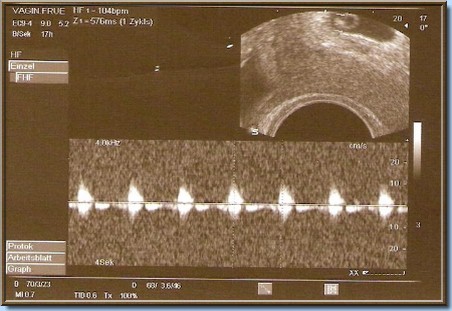

Unser kleiner Zwerg

in der 6.SSW